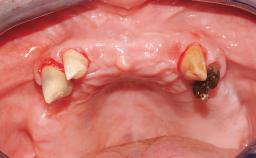

A 68-year-old, completely edentulous male patient presented for evaluation and treatment options. He reported excellent general health and was taking no regular medication. He had been edentulous for approximately 12 years, having lost his teeth to periodontal disease and dental caries. The patient’s chief complaint was incompetent function. His secondary concerns included his appearance and the desire for a predictable outcome. He attributed his reduced functional capacity to his lower complete denture, which he described as poor. He was particularly concerned with the denture’s instability and poor fit. In general terms, he was satisfied with the maxillary complete prosthesis. The maxillary prosthesis was characterized by adequate retention, stability, and support, although the fit was considered less than ideal.

Case Type Edentulous Mandible

# of Implants 6